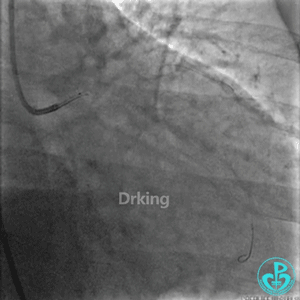

7F EBU指导导管到达左冠开口,把Sion导丝送至LAD远段,先后在微导管、双腔微导管、抽吸导管及2.5×20mm、3.0×15mm球囊堵闭LAD开口等各种技巧辅助支撑下,尝试Sion、BMW、Intuition、XT导丝反复塑形调整均未能通过LCX近段扭曲处送至远段。其间采用了球囊锚定、双腔微导管支撑、抽吸导管支撑、导丝塑成天鹅颈形状等技术。

经反复尝试失败后,发现由于LAD血管较粗,且LCX严重扭曲角度刁钻,而且不止一个高度弯曲(2处),以上技术实施时预进入LCX的导丝仍然会被弹入LAD。